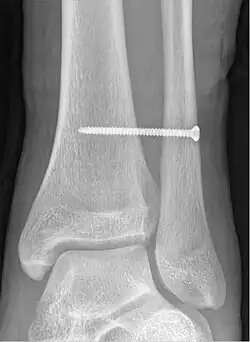

À la suite d'un traumatisme de type fracture, les syndesmoses peuvent subir des lésions ligamentaires comme des déchirures, en particulier pour les syndesmoses tibio-fibulaire et radio-ulnaire. Ces lésions peuvent exiger une réparation chirurgicale en fonction de leur degré de gravité.